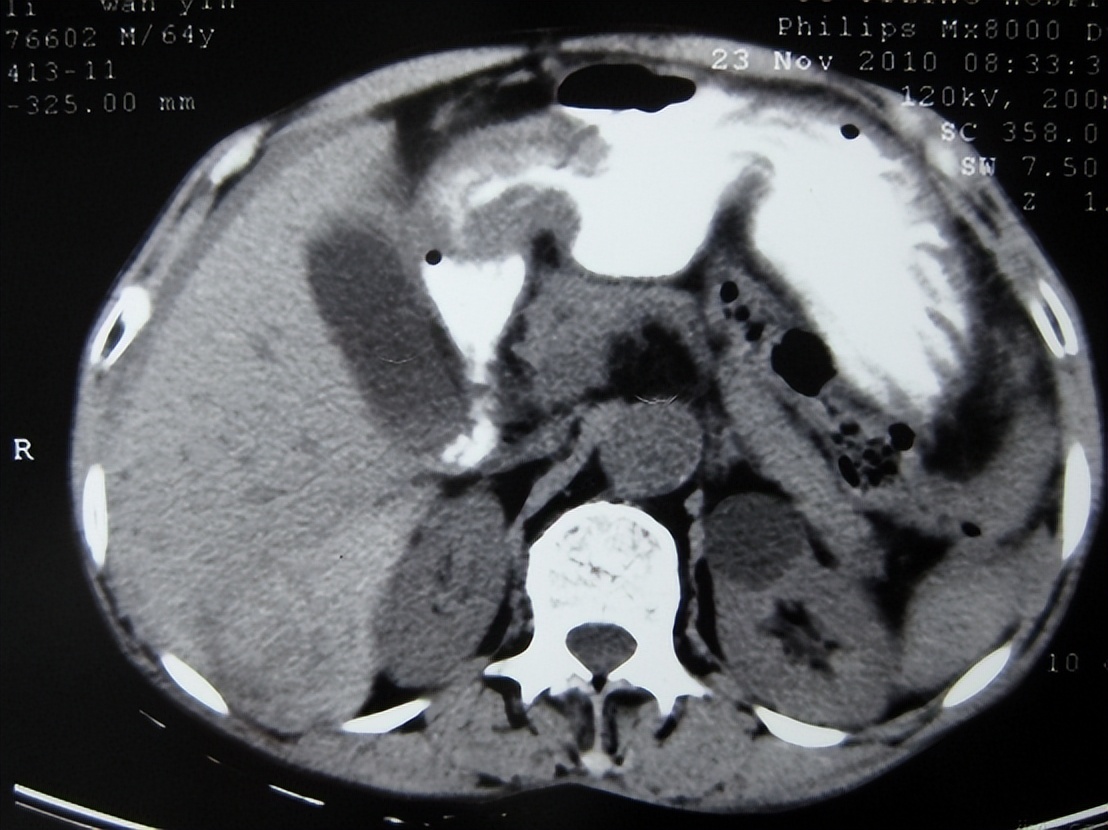

3.腹部CT

CT不仅可以提高少量气腹的诊断率,而且能对多种原发病做出诊断,对外科及时合理治疗提供依据。但由于CT检查耗时相对较长、费用相对较高、辐射量相对较大,所以目前在新生儿胃肠穿孔方面的应用并不普遍。